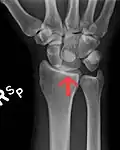

![]() The left lunate bone | |

The lunate is a crescent-shaped carpal bone found within the hand. The lunate is found within the proximal row of carpal bones. Proximally, it abuts the radius. Laterally, it articulates with the scaphoid bone, medially with the triquetral bone, and distally with the capitate bone. The lunate also articulates on its distal and medial surface with the hamate bone.[2]: 708 [3]

Bone

The proximal surface of the lunate bone is smooth and convex, articulating with the radius. The lateral surface is flat and narrow, with a crescentic facet for articulation with the scaphoid bone. The medial surface possesses a smooth and quadrilateral facet for articulation with the triquetral bone. The palmar surface is rough, as is the dorsal surface. The dorsal surface is broad and rounded. The distal surface of the bone is deep and concave.[4]